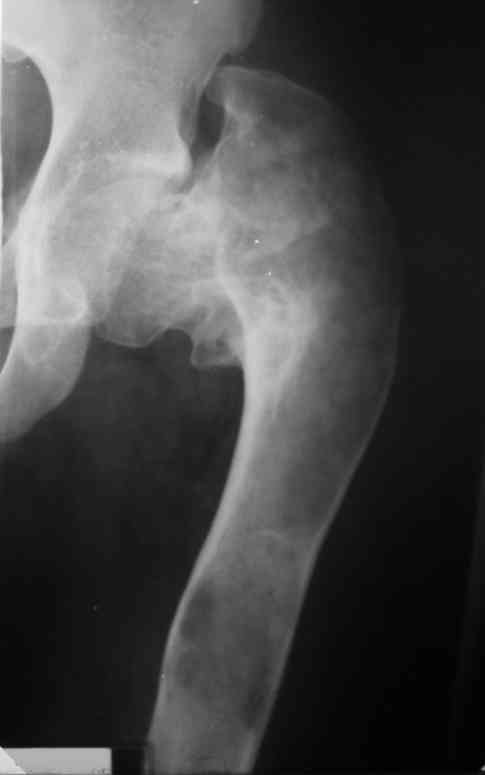

Около 16 лет наблюдаю пациента с ФИБРОЗНОЙ ДИСПЛАЗИЕЙ левой нижней

конечности, полиосальная форма. Прилагаю рентгенснимки. Рекомендую

Имя     : Levoe bedro,1991 god[1]..JPG